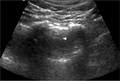

Images

Normal

Abnormal